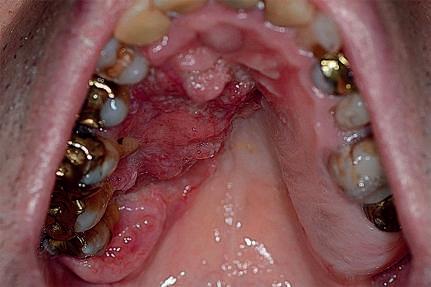

Vegetação

Vegetações são lesões sólidas, elevadas, salientes, cônicas, lobulares, filiformes ou com aspecto de couve-flor, de consistência mole e agrupadas em maior ou menor quantidade (Fig. 1-13).

Exemplos: hiperplasia papilar palatina, condiloma acuminado, leishmaniose, carcinoma de células escamosas, paracoccidioidomicose, verruga vulgar.